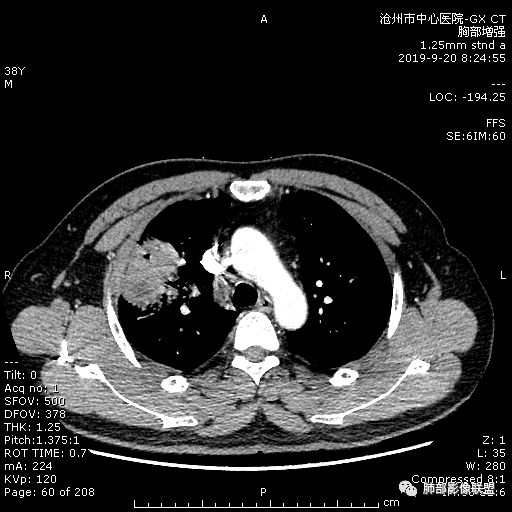

青年男性,肿瘤指标无异,右上中肺团片影,形态不规,跨叶生长,

病灶内见坏死,增强边缘强化,考虑炎性肉芽肿,TB,鉴别鳞。

年轻男性,咳嗽2月,痰中带血,胸痛,炎症指标稍高,肿标正常。影像,右肺上叶不规则团块影,浅分叶,伴边界不清磨玻璃影,从外周向内分布,局部胸膜增厚,病灶中央坏死,坏死边界尚清,空洞形成,空洞内壁光滑;考虑炎性肉芽肿性病变,结核可能,鉴别恶性肿瘤及真菌感染。病灶分布特点不考虑隐球。

右肺上叶不规则病灶,密度不均,有分叶,边缘不清,中央有坏死,坏死壁尚光滑,增强壁有强化,病灶有外朝内,整体收缩为主,慢性病程,考虑炎性病变,肺脓肿或者结核,淋巴结肿大,支气管截断,胸膜脂肪间隙变窄,加个鉴别恶性肿瘤。

右上肺占位,总体膨胀性生长,支气管截断,坏死明显,常规考虑鳞。

38岁,男性,慢性咳嗽2月,右胸痛8天,无发热;白细胞高,肿瘤标志物不高;右上肺不规则块状影,周围有磨玻璃影,边界清,整体有膨胀感,分叶,与胸膜糊墙,并见栽赃,增强肿块中央坏死,周边强化。综合考虑,考虑恶性,鳞癌可能。

38岁,男性,慢性咳嗽2月,右胸痛8天,无发热。白细胞高,肿瘤标志物不高。右上肺不规则块状影,周围有磨玻璃影,边界模糊,整体有膨胀感,分叶,与胸膜糊墙,可疑栽赃,增强肿块中央坏死,边界清,周边强化明显,强化区有低密度影,壁不规则,跨叶生长,支气管截断,伴支气管扩张,综合考虑腺癌

中年男性,咳嗽2月,伴胸痛8天,少许痰血,无发热中性粒明显增高,低氧,肿标不高,右肺上叶不规则实性肿块,深分叶,局部凹陷呈月牙铲改变,多坏死,多空泡,前段支气管分支似见堵塞,2R、4R、10R和7区淋巴结肿大。考虑肺癌可能,建议支气管镜活检

晨读病例,右肺上叶胸壁处占位,边缘分叶毛刺,收缩力强,多发坏死,远端支气管截断,不均匀性强化,血管穿行变窄,纵隔多发淋巴结肿大,考虑恶性肿瘤,首先考虑腺癌

首先病灶示:跨尖、后、前三段,局部突入中叶;大家理解一下:是不是光滑的地方有叶裂,毛糙的地方没叶裂。